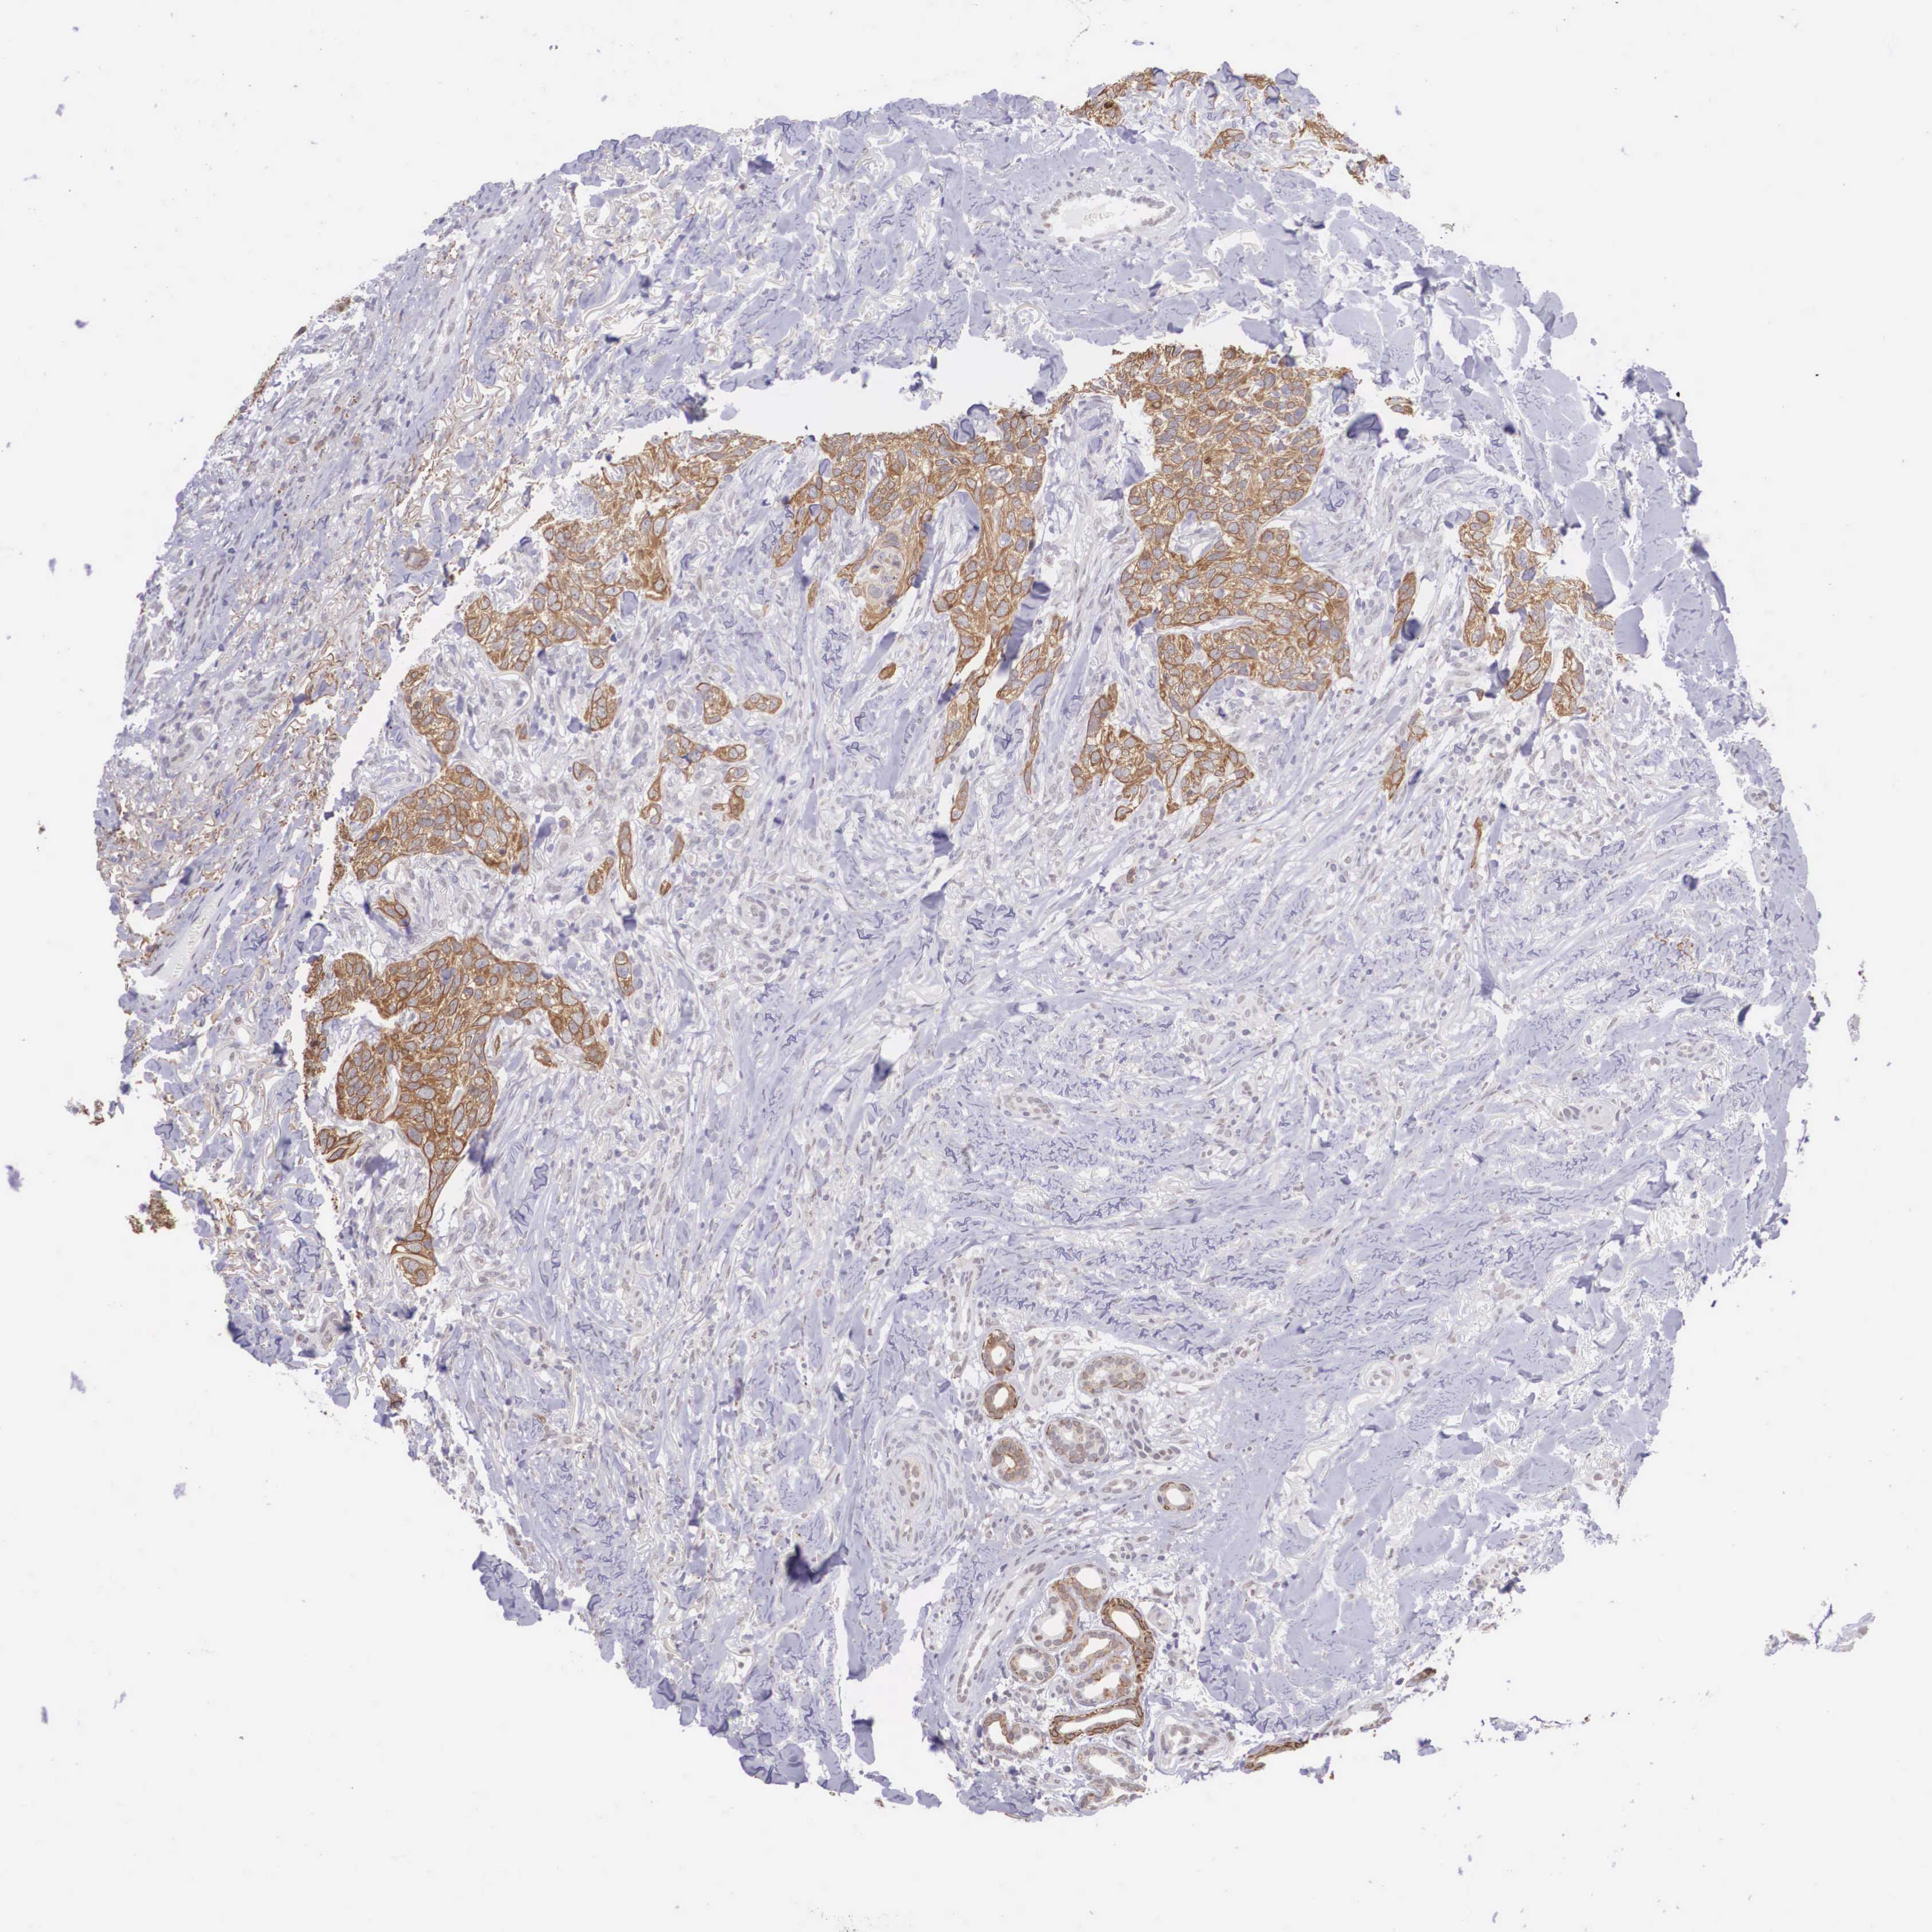

SKIN CANCER - Protein expressioni

A mouse-over function shows sample information and annotation data. Click on an image to view it in a full screen mode. Samples can be filtered based on level of antibody staining by selecting one or several of the following categories: high, medium, low and not detected. The assay and annotation is described here.

Antibody staining in the annotated cell types in the current human tissue is reported as not detected, low, medium, or high, based on conventional immunohistochemistry profiling in selected tissues. This score is based on the combination of the staining intensity and fraction of stained cells.

Each image is clickable and will lead to virtual microscopy that enables deeper exploration of all samples and also displays staining intensity scores, fraction scores and subcellular localization as well as patient and tissue information for each sample.

Antibody HPA000662

Staining

High

Intensity

Strong

Quantity

>75%

Location

Nuclear

Cytoplasmic/membranous

Squamous cell carcinoma, NOS

Basal cell carcinoma